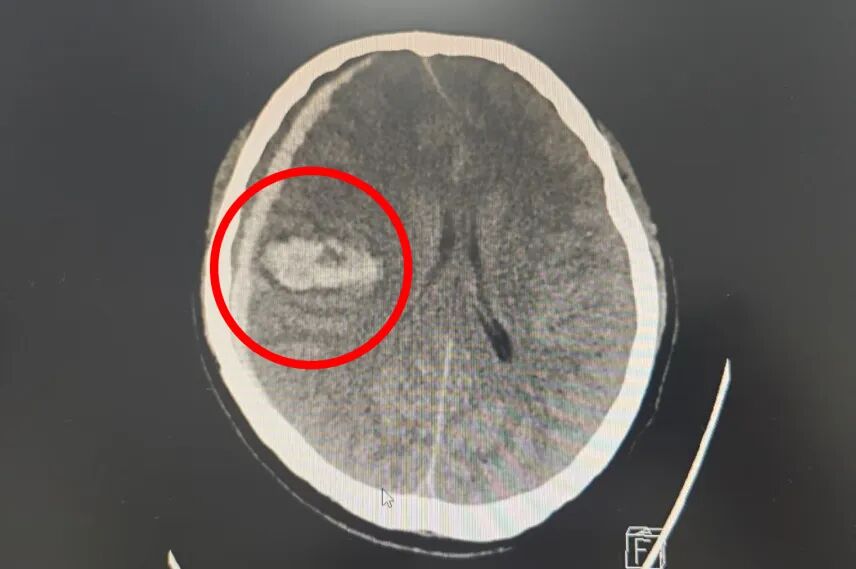

主任医师

神经外科主任

擅于颅内肿瘤、椎管内肿瘤及血管病的显微手术治疗;对各种颅脑外伤尤其是重型脑损伤的诊断、治疗及康复处理具有丰富的临床经验。运用微创技术治疗脑血管病、自发性颅内出血、外伤性颅内出血积累了丰富的临床经验;尤其擅长颅内及椎管内肿瘤、脑血管病、脑出血的微创手术治疗。